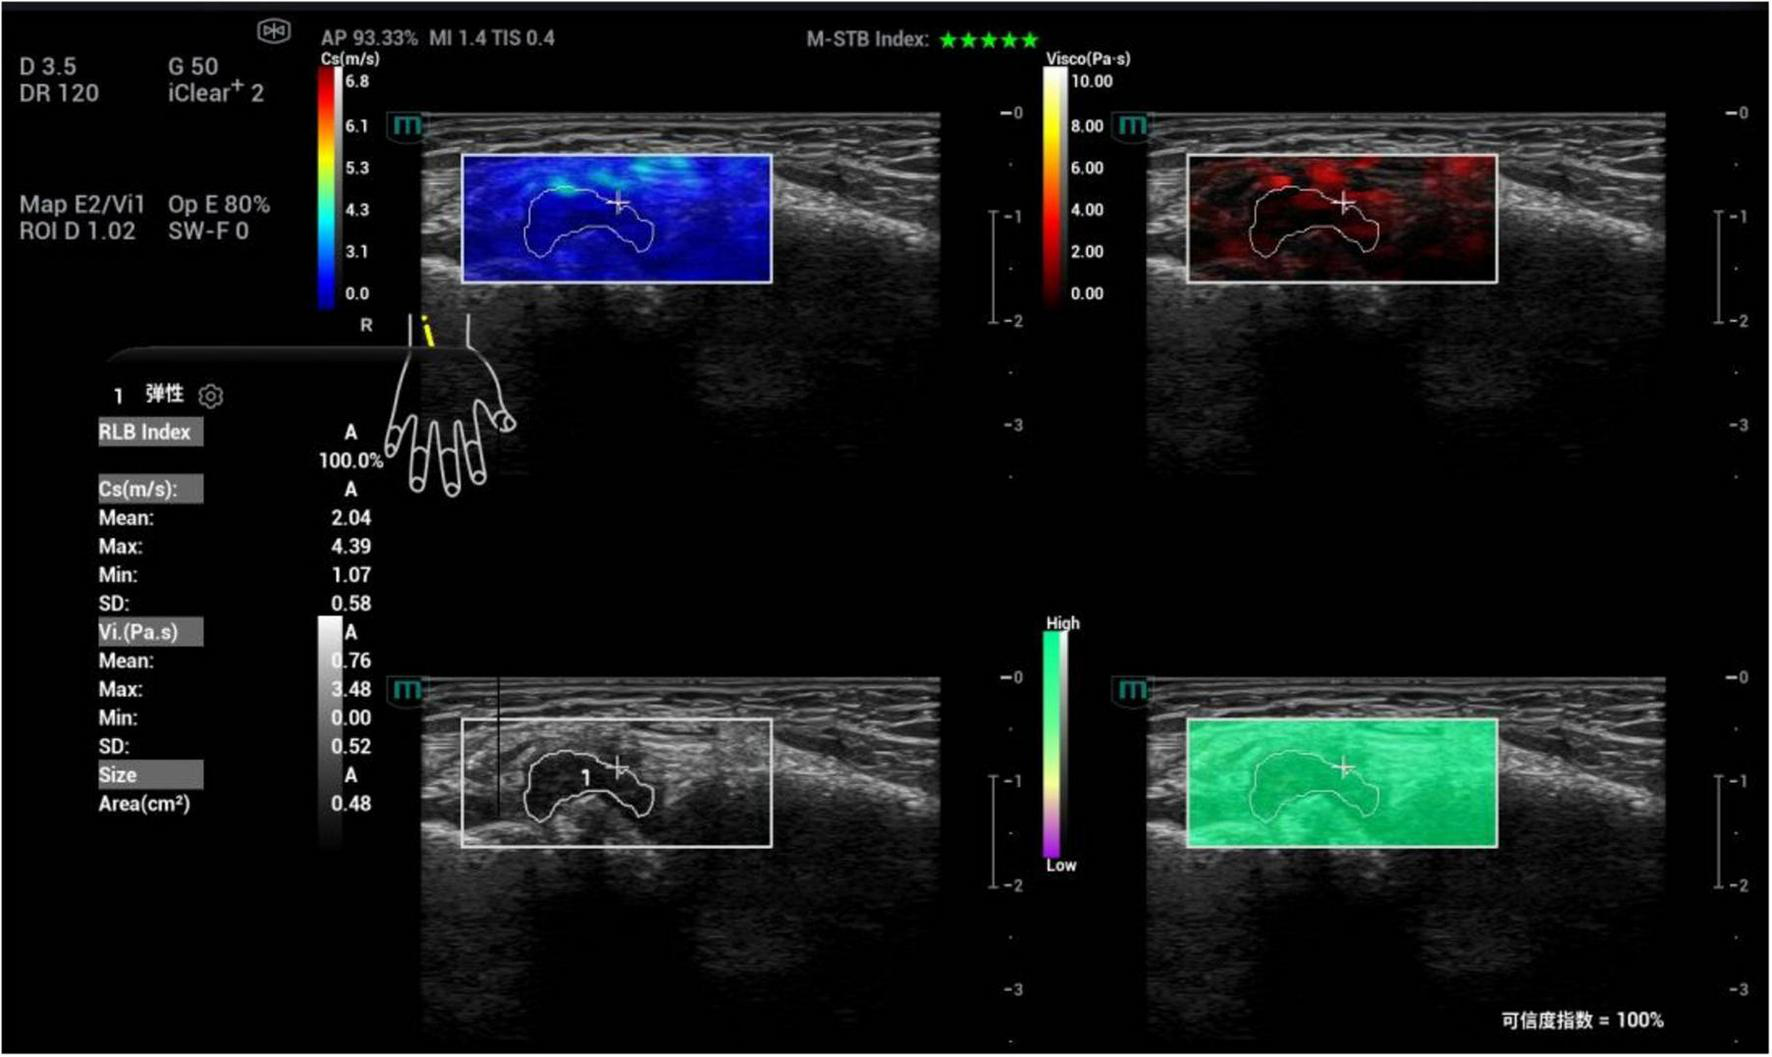

FIGURE 3

Schematic diagram of viscoelastic images (measurement of shear wave velocity and dispersion coefficient in the first metatarsophalangeal joint of the right foot). (a) (top left) Shear wave elasticity image; (b) (top right) Dispersion coefficient image; (c) (bottom left) Grayscale ultrasound image; (d) (bottom right) Reliability map (RLB).

Among the single parameters, Cmean showed the highest diagnostic efficacy, with an AUC of 0.836 (95% CI 0.774∼0.897). The optimal cut-off value was 2.36 m/s (Figures 4, 5), at which the sensitivity and specificity for diagnosing AG were 81.4% and 71.6%, respectively. The AUC of the GEE model was 0.885 (95% CI 0.833∼0.938), with an optimal cutoff value of 0.41, and the corresponding sensitivity and, specificity for diagnosing AG were 87.1% and 76.5%, respectively (Table 4).

Ultrasound viscoelastic image of the right wrist joint in a patient with rheumatoid arthritis. A 60-year-old male patient. Ultrasound viscoelastic imaging showed that the thickened synovium of the right wrist joint had a Cmean of 2.04 m/s (<cutoff value of 2.36 m/s) and a Vmean of 0.76 Pa⋅s (<cut-off value of 0.81 Pa⋅s).